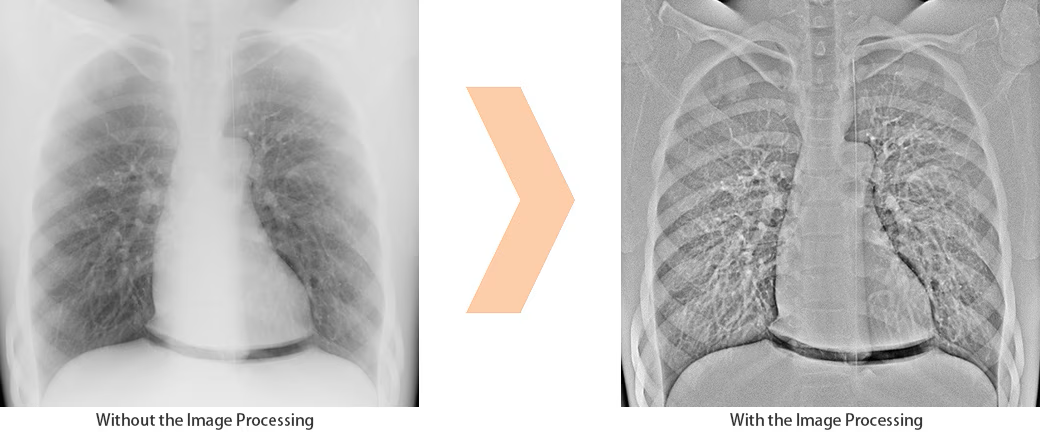

Edge Enhancement / Kantenanhebung OPTION

Bei chirurgischen Eingriffen hilft die neue Bildverarbeitungsfunktion dabei, sicherzustellen, dass keine medizinischen Artikel wie Mull und Nadeln zurückbleiben. Dies ist auch nützlich, um die Position der Katheterspitze bei PICC-Einführungsverfahren deutlicher zu überprüfen.